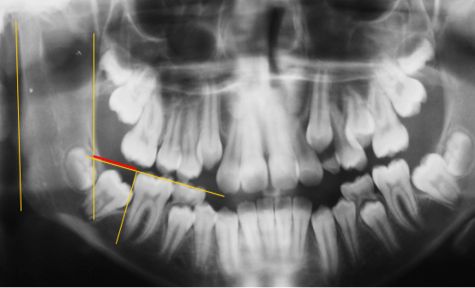

La muestra se compuso de 370 fichas clínicas que cumplieron los criterios de inclusión. Finalmente 740 segundos molares inferiores permanentes fueron analizados. Las variables medidas fueron ángulo del segundo molar (Fig.1), ángulo del primer y segundo molar inferior permanente respecto al plano oclusal (Fig. 2), invasión del espacio distal del primer molar por el segundo molar (Fig. 3), distancia entre el borde distal del primer molar y el borde anterior de la rama (Fig. 4).

Se midió además la distancia entre el punto de contacto mesial del segundo molar y el punto amelocementario distal del primer molar permanente. Para medir el ángulo del segundo molar se trazaron dos líneas, una en el centro del eje axial del primer molar y la otra en el segundo y para objetivar el trazado de estas líneas se determinó un punto medio coronal, uno cervical y otro apical en ambos molares (Fig.1). Para determinar los ángulos con respecto al plano oclusal se usaron las líneas centrales del eje axial de los molares y una línea trazada sobre el plano oclusal en el lado derecho y otra en el lado izquierdo (Fig. 2).

Fig. 1 Ángulo de inclinación entre 1º y 2º molar inferior permanente

La muestra se compuso de 370 fichas clínicas que cumplieron los criterios de inclusión. Finalmente 740 segundos molares inferiores permanentes fueron analizados. Las variables medidas fueron ángulo del segundo molar (Fig.1), ángulo del primer y segundo molar inferior permanente respecto al plano oclusal (Fig. 2), invasión del espacio distal del primer molar por el segundo molar (Fig. 3), distancia entre el borde distal del primer molar y el borde anterior de la rama (Fig. 4).

Se midió además la distancia entre el punto de contacto mesial del segundo molar y el punto amelocementario distal del primer molar permanente. Para medir el ángulo del segundo molar se trazaron dos líneas, una en el centro del eje axial del primer molar y la otra en el segundo y para objetivar el trazado de estas líneas se determinó un punto medio coronal, uno cervical y otro apical en ambos molares (Fig.1). Para determinar los ángulos con respecto al plano oclusal se usaron las líneas centrales del eje axial de los molares y una línea trazada sobre el plano oclusal en el lado derecho y otra en el lado izquierdo (Fig. 2).

Fig. 1 Ángulo de inclinación entre 1º y 2º molar inferior permanente